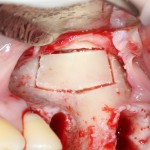

— образовавшимся при создании доступа костным фрагментом, при необходимости, можно закрыть даже большую перфорацию:

В контексте сегодняшней темы было бы важнее рассмотреть место и форму апертуры доступа.